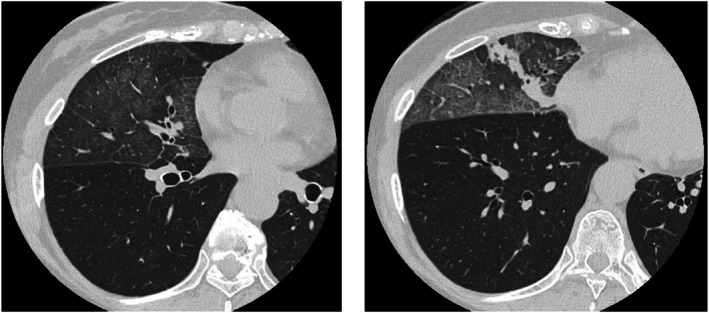

一位70岁的女性患者被诊断为IV期egfr突变型非小细胞肺癌,在接受化疗时经历了三种不同的外源性脂质肺炎。胸部CT一致显示毛玻璃混浊,呈疯狂铺路状,支气管镜检查证实脂质,cd163阳性泡沫巨噬细胞的存在。值得注意的是,每次发作都与不同的外源性暴露有关:鼻内施用凡士林,长时间使用煤油加热器,随后鼻内使用骏马润肤油。所有的发作都发生在右中叶,并在停止发作剂后得到解决。这是首例由多种不相关物质引起的单一患者复发性外源性脂质性肺炎的报道。该病例强调了放射学模式的诊断价值,细致的暴露史的重要性,以及在癌症治疗期间考虑新浸润患者的其他病因的必要性。

A 70-year-old female patient diagnosed with stage IV EGFR-mutant non-small-cell lung cancer experienced three distinct instances of exogenous lipoid pneumonia while undergoing chemotherapy. Chest CT consistently revealed ground-glass opacities with a crazy-paving pattern, and bronchoscopy confirmed the presence of lipid-laden, CD163-positive foamy macrophages. It is noteworthy that each episode was associated with a distinct exogenous exposure: intranasal administration of petroleum jelly, prolonged utilisation of a kerosene heater, and subsequently, intranasal application of Junma Moisturising Oil. The localisation of all episodes to the right middle lobe was noted, and resolution was attained with the cessation of the offending agent. This is the first reported case of recurrent exogenous lipoid pneumonia in a single patient caused by multiple unrelated substances. This case underscores the diagnostic value of radiologic patterns, the significance of meticulous exposure history, and the necessity of contemplating alternative aetiologies in patients with new infiltrates during cancer therapy.